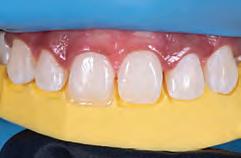

A 31-year-old woman presented with cosmetic concerns regarding her smile and requested a conservative enhancement. After clinical and radiographic analysis, digital 35mm photographs were taken and reviewed by the restorative clinician, technician, and surgeon (Fig 1). A digital impression was taken of the maxillary and mandibular arches using an intraoral scanner (Trios 3, 3Shape; Fig 2), and a smile design was developed with NemoSmile Design 3D software (Nemotec; Fig 3a). This allows for a facially driven smile frame to be created using reference lines of facial and smile proportions and natural teeth shapes and textures from the digital library (Fig 3b).

After developing the simulated mock-up, a 3D-printed resin model was created using CAD software (Fig 4a), and a clear PVS matrix (Exaclear, GC America) was fabricated to replicate the printed diagnostic wax-up using a nonperforated tray (Fig

Fig 1 Preoperative clinical views of a 31-year-old woman presenting with diastemas and limited tooth visibility. (top) Portrait. (center row) Intraoral views. (bottom row) Smile.

4b). This matrix was used to create an intraoral motivational mock-up with bis-acryl composite (Luxatemp Ultra, DMG). This additive mock-up provides the interdisciplinary team with an intraoral translation for evaluation (Fig 5). Upon evaluation of the digital smile frame and the clinical translation, it was determined that multiple esthetic and restorative requirements were necessary for an optimal biologic framework, and the interdisciplinary team determined the best sequence for these procedures. The patient was presented with the interdisciplinary treatment possibilities that included restoring the maxillary anterior teeth and premolars with a minimally

invasive preparationless procedure or with less conservative veneer preparations. The restorative materials discussed included injectable resin composites and ceramic (ie, feldspathic, pressable, machinable). For an optimal biologic framework and health, it was determined that connective tissue grafting would be necessary for treatment of the recessiontype defects on the maxillary left central and lateral incisors, canine, and premolars. The patient opted for the conservative preparationless composite veneers using the injectable resin technique followed by a connective tissue surgical procedure using the tunneling technique.